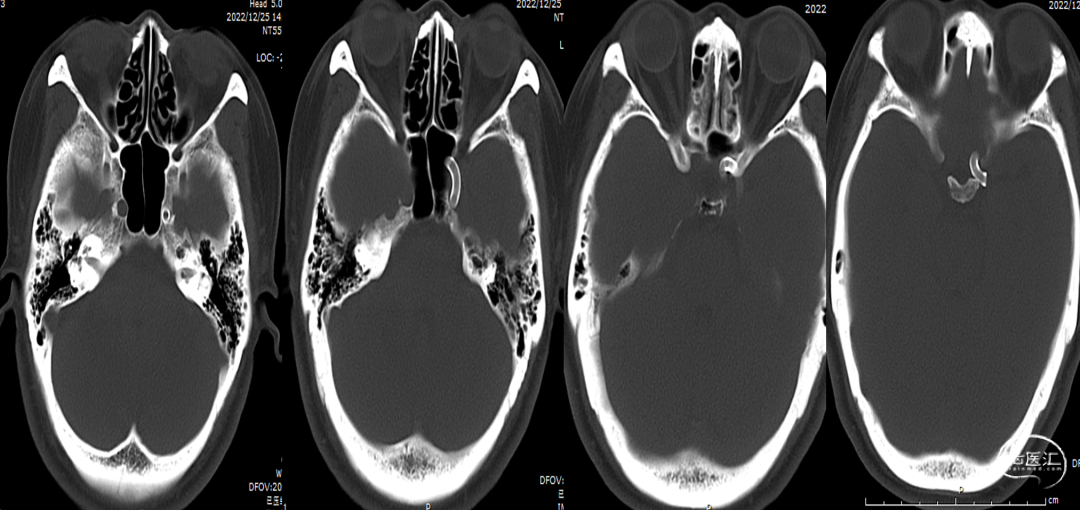

术后复查右颈内动脉造影(2022-12-27)

复查左颈内动脉造影(2022-12-27)